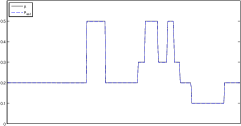

The data (see Figures 1 and 2) was generated in the diffusion model (1.2) using self-written (linear-basis) finite element code in MATLAB. For both examples, we took and used a uniform boundary condition . The simulated data were generated on a -grid and then down-sampled (by averaging) to to avoid inverse crime. After that, Gaussian noise with different intensities (standard deviations of and of the average signal value ) was added to the data.

The edge detector is used to detect jumps in the derivatives of the data up to second order (to obtain an initial estimate of the parameter jump set ). Since this process is highly sensitive with respect to noise, we varied the edge detection procedure subject to the amount of noise in the data. In the noise-free examples, we estimated the jumps of all three functions , that is, jumps of derivatives of up to second order. We restricted the jump estimation to for the low-noise examples (i.e., jumps of derivatives up to first order) and in the high-noise examples (only jumps in the data itself).

Reconstruction results and error profiles at different noise levels can be seen in Figures 3 and 4. In both examples, the noise-free reconstructions are very accurate and contain mostly smoothing error. In the low-noise reconstructions, due to the fact that more regularization is necessary, some of the parameter variation is underestimated. In the high-noise examples, most detail in is lost since a lot of regularization is required to get reasonable results. The fine detail in can, however, still be recovered very accurately in both examples.